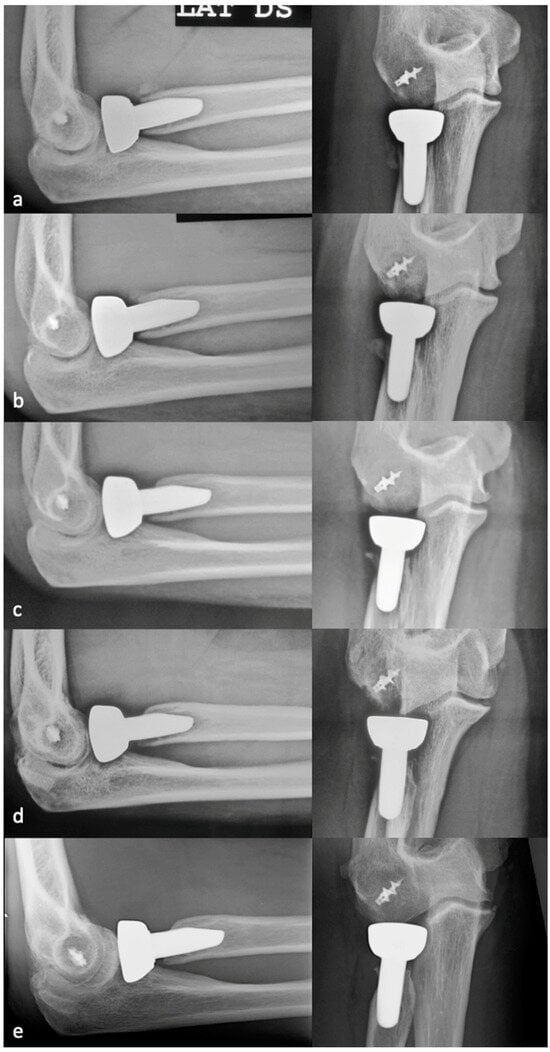

No implant-related complications were detected at the last radiographic evaluation. No patients underwent reintervention during the follow-up owing to stem failure-related complications. Three patients suffered a disassembly of a bipolar prosthesis 4, 5, and 10 years after the index procedure following a new trauma. In the first patient, the radial head component was replaced and the LCL was reconstructed. In the second and third patients, the disassembly was associated with capitellar fracture; these two cases both underwent osteosynthesis with two headless screws and replacement of the radial head component. The mPRNR was moderate in one of these three patients, severe in another, and moderate in the last. The stem appeared to be well integrated in all three cases, with no need for revision (Figure 5).

Figure 5.

Clinical case of a patient who experienced disassembly of a bipolar prosthesis 10 years after the index procedure following a new trauma. The disassembly was associated with a capitellum fracture (white arrowhead) (a); the mPRNR in this patient was moderate. The stem appeared to be well integrated, with no need for stem revision (b). The intraoperative appearance of PRNR is also shown in (b) (white arrows). Osteosynthesis with two headless screws and replacement of the radial head component were performed (c,d).